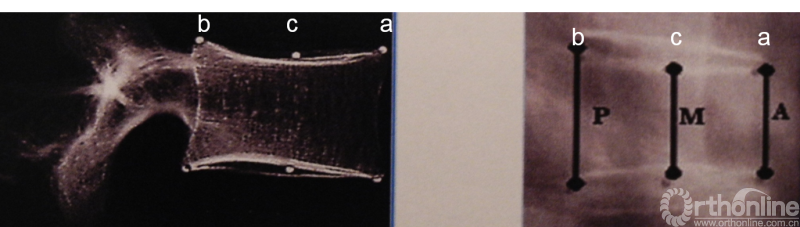

骨质疏松性脊柱骨折的X线表现为普遍性密度减少(随骨质疏松严重程度增加而增加);“画框样”椎体,椎体透光度与上、下终板皮质成分的反差明显的增加;骨质疏松椎体骨折后形状的改变可分:楔形、双凹形、压缩形。

其根据椎体前缘高度(a)、椎体后缘高度(b)、椎体中央高度(c)之间比值确定椎体分类。楔形椎表现为a比b减少25%以上(<25%轻度;26-39%中度;≥40%重度);双凹椎(鱼椎)表现为当c比a、b减少20%;压缩椎表现为a、b、c均较上位及下位椎体的a、b、c减少20%以上。